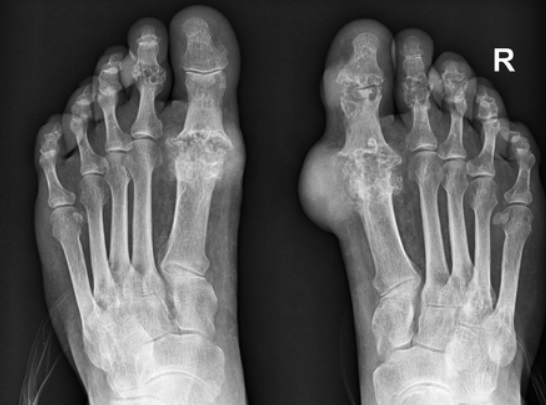

통풍은 요산이 체내에 가득하게 쌓이면서 생기는 질환입니다. 요산은 우리가 먹은 음식이 소화되고 최종적으로 남은 물질로 혈액 내 녹아 소변으로 배출되는데 요산이 과도하게 쌓이면 결정체로 변하게 되고 이 결정체가 관절 내에 침착하여 염증을 유발하게 되기 때문에 이번 시간에는 통풍 증상과 통풍 치료법에 대해 알아보도록 하겠습니다.

통풍 증상 두 번째는 엄지발가락 통증입니다. 처음에 주로 엄지발가락 근저부 관절에 발병하는데 돌발적인 통증과 함께 붉게 부어오르며 무릎, 손목, 발목, 팔꿈치 등에 발생하기도 합니다.

통풍 증상 네 번째는 급성 통풍 발작인데 엄지발가락, 발목 등 한 곳의 관절이 갑자기 빨갛게 부어오르고 손댈 수 없을 정도로 통증이 심한데 발뒤꿈치, 팔목, 손가락, 귀 등에서 나타나며 급성 통풍성 관절염이라고 부르기도 합니다.

통풍 증상 아홉 번째는 만성 관절염입니다. 통풍이 방치되면 발작성 관절염의 빈도가 점점 잦아지고 침범하는 관절 수도 많아집니다. 회복하는 속도도 더욱 더뎌지고 관절염이 만성으로 발전할 수 있습니다.